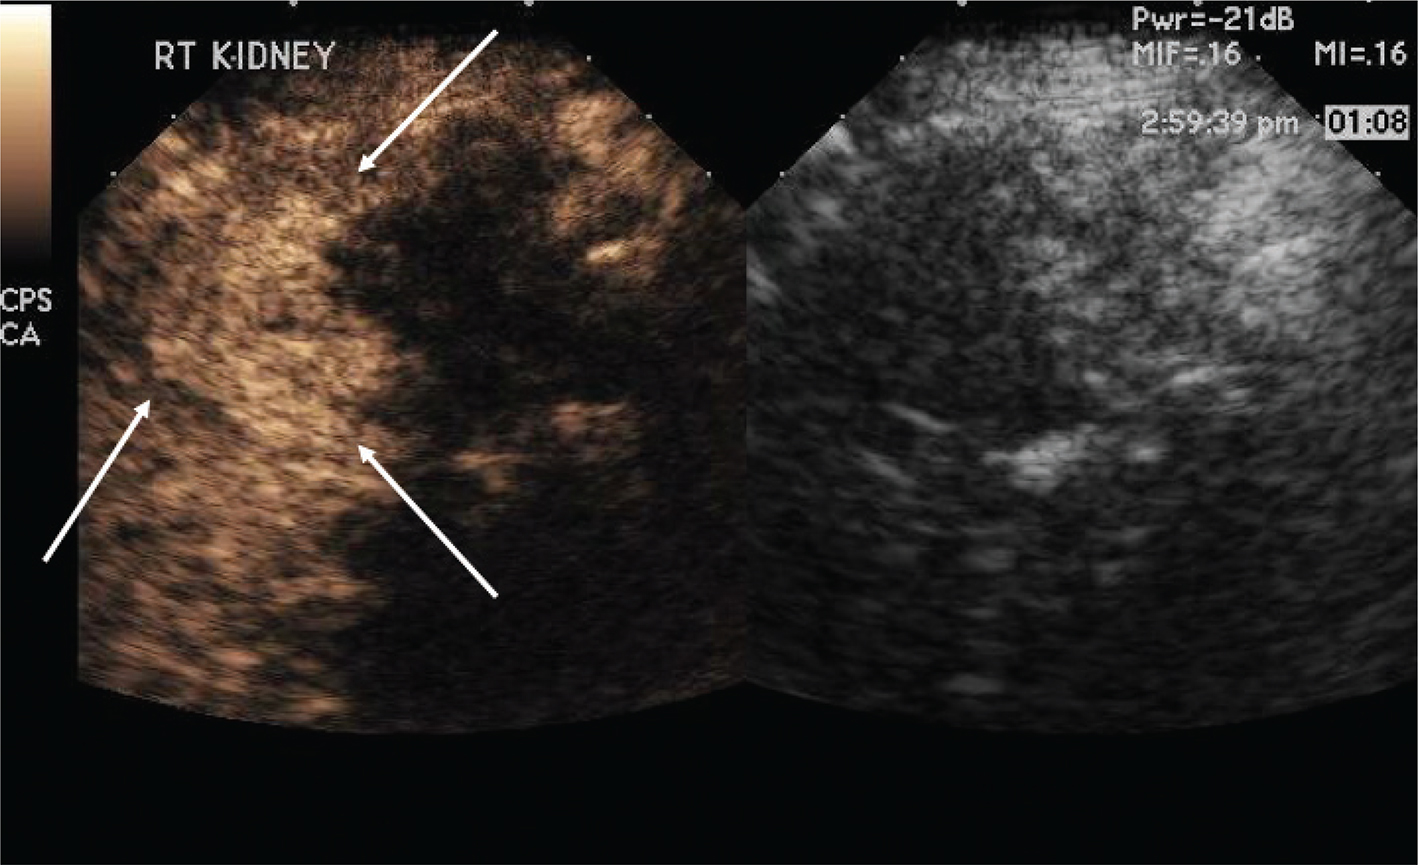

Figure 2 demonstrates that after the first ablation, a second dose of ultrasound contrast can be performed to evaluate for residual tumor. The CEUS contrast lasts for about 5 min. During the RFA, gas bubbles are generated and appear as CEUS contrast when imaging. Waiting for about 5 min after the completion of the ablation will eliminate this problem. If bubbles still remain in real-time CEUS imaging, the bubbles generated from the procedure will not move whereas the UCA bubbles in residual tumor will be visualized as moving. In this case, a large area of residual tumor (arrows) remains. The CEUS image can be used to reposition the RFA needle into the residual tumor.

Fig 2

Figure 2. Multiple doses of ultrasound contrast can be administered during the RFA procedure. The contrast agents last for about 5 min so that residual enhancement is not present on additional doses. In this case, a CEUS study was performed after the first ablation. Note that there is residual tumor (arrows). The RFA needle can then be repositioned into the residual tumor for additional ablation. This confirms that the tumor is completely ablated at the first setting. The similar process cannot be performed in CT because only one dose of CT contrast can be administered.